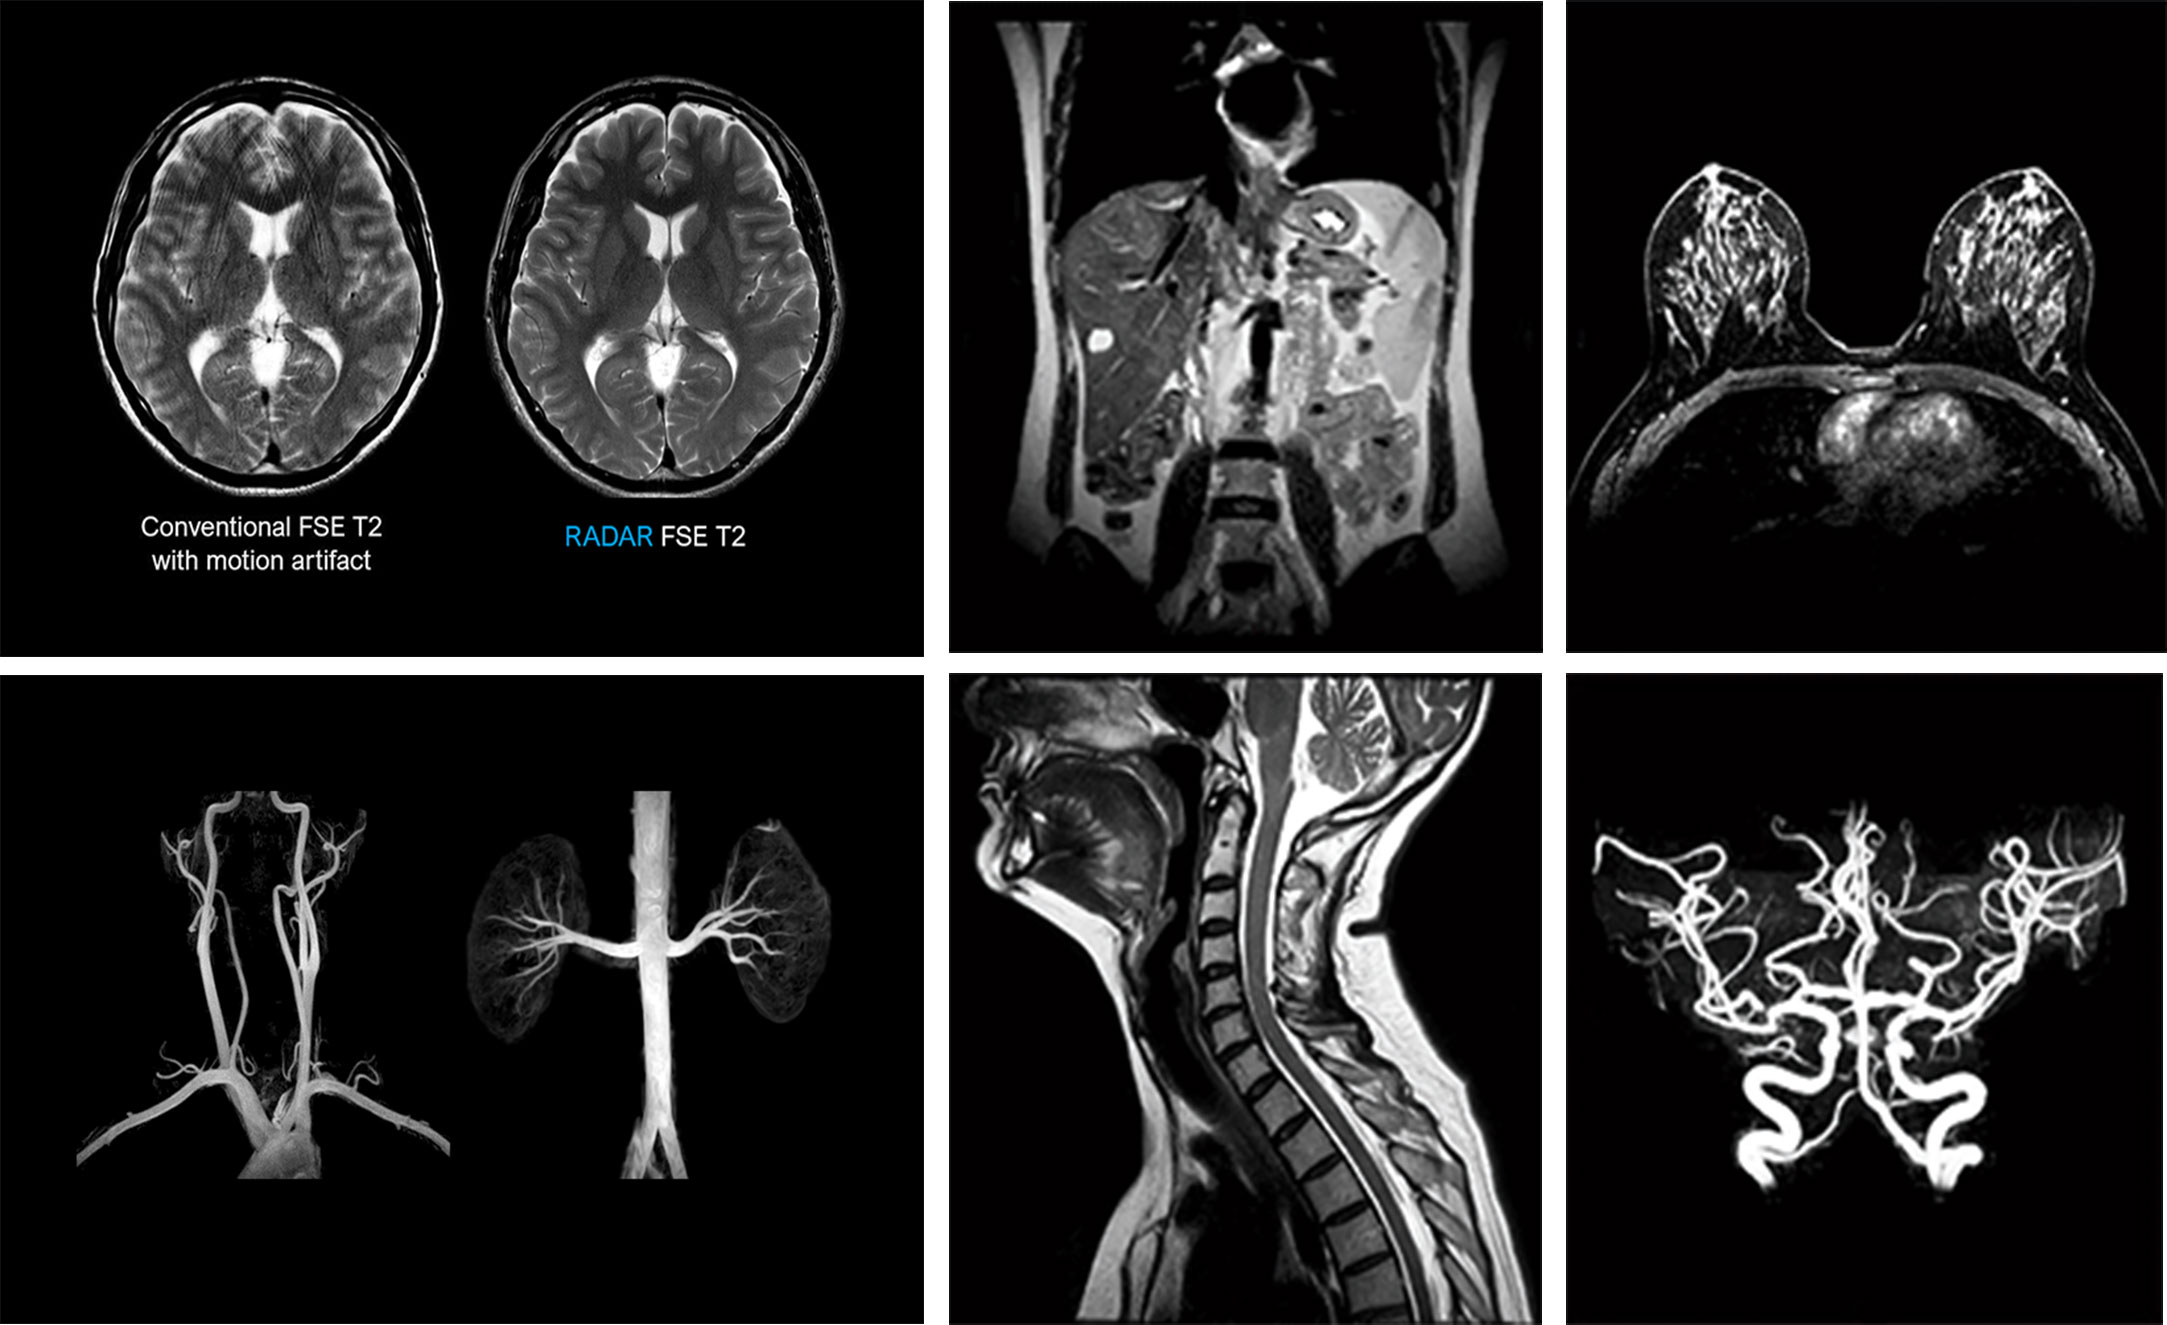

Beyin MR

Boyun MR

Bel MR

Diz MR

Omuz MR

Tüm kas-iskelet sistemi görüntülemeleri

Karın ve pelvis incelemeleri

Yapay Zekâ Destekli Hızlı MR (FastMR Teknolojisi)

✔ Ortalama %30-40 daha kısa çekim süresi

✔ Daha az gürültü (noise)

✔ Daha net ve yüksek çözünürlüklü görüntüler